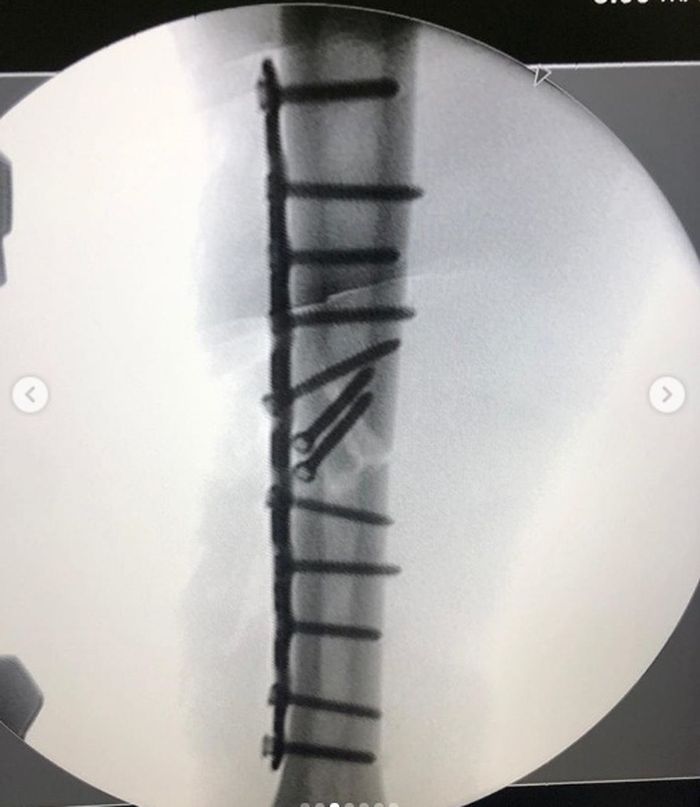

Unggah foto rontgen setelah dipasang 12 baut di tulang humerus kanan, Marc Marquez buktikan cedera yang dialaminya serius

Lalu pada foto berikutnya terlihat hasil operasi yang mana terdapat 12 baut dan sebuah pelat titanium untuk mengembalikan posisi tulang lengan atas